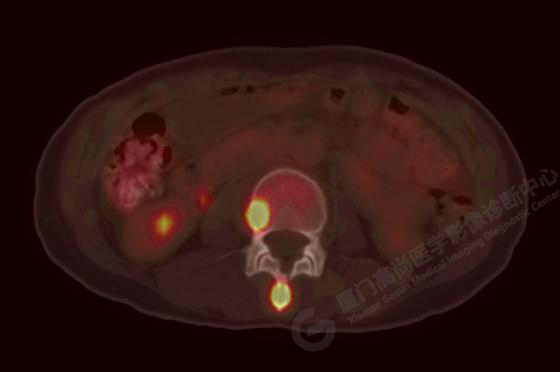

病例3:某女,47歲,咳嗽3周,無咯血,右上胸部疼痛,腰部疼痛

廈門市醫(yī)院查血腫瘤標(biāo)記物,CA153、CA724、CA211、NSE、AFP、CEA、CA125均正常

右肺上葉前段實(shí)性腫塊,大小約3.2x2.7x2.6cm,邊緣見毛刺、分葉,胸膜牽拉明顯,前段支氣管阻塞。FDG攝取增高,SUVmax,16.8;右側(cè)頸部Ⅳ區(qū)、右側(cè)鎖骨區(qū)、右肺門及縱隔淋巴結(jié)腫大, FDG攝取增高,SUVmax7.9;C2、L2椎體、右側(cè)第6肋骨、骶骨、髂骨、左側(cè)髖臼、腰椎體及附件骨質(zhì)破壞,SUVmax11.8。

影像診斷:右肺上葉周圍型肺癌并多發(fā)淋巴結(jié)、骨骼轉(zhuǎn)移。(TNM分期,T2aN3M1c  Ⅳ B期)

病理診斷:低分化腺癌